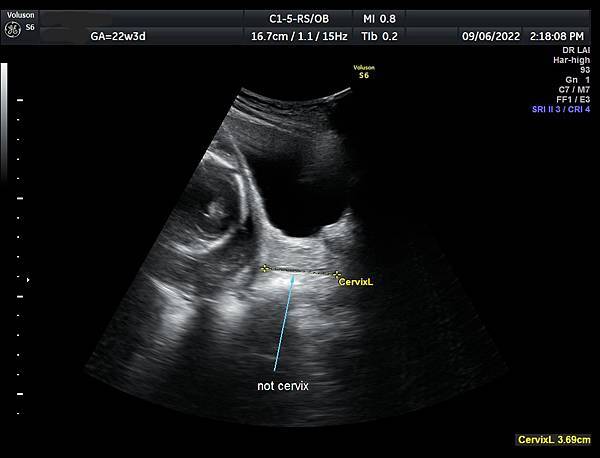

• 孕兒診所賴錫鉅醫師 384 讓我嚇一大跳的case : 如何避免子宮頸長度測量錯誤

讓我嚇一大跳的case

如何避免子宮頸長度測量錯誤